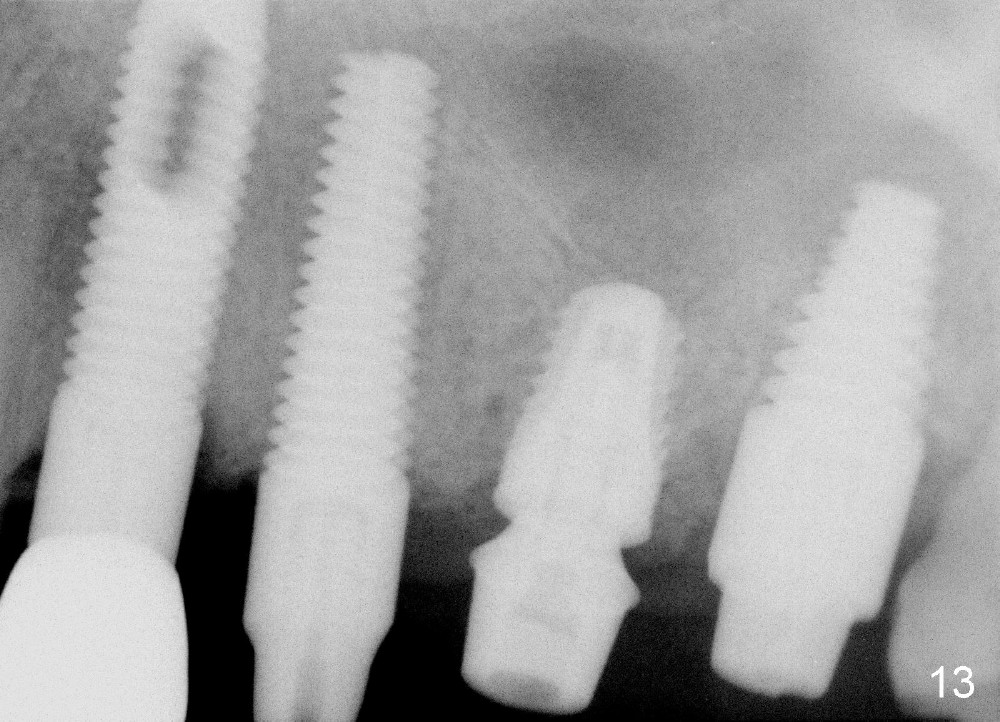

In fact this senile patient unintentionally uses the provisional as a permanent restoration and chews bone on the left side, since at the same time implants at the sites of #29 and 30 are not restored.  Two and a half months post implantation at #13 and 15, the patient returns because the provisional has fractured (Fig.14), while all of the 3 implants are stable with sign of osteointegration (Fig.13).  The patient requests early final restoration, which is honored.  After fabrication of a new temporary bridge, he eats like a dog!